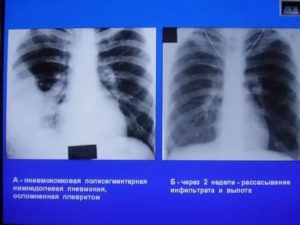

Общий анализ крови при пневмонии показывает наличие лейкоцитоза со сдвигом лейкоформулы влево, повышение СОЭ. Рентгенологическое исследование при полисегментарной пневмонии выявляет очаги инфильтрации (затемнения) в нескольких сегментах одного или двух легких.

При левосторонней пневмонии в нескольких сегментах на рентгеновском снимке должны быть видны множественные очаги воспалительного процесса, локализация которых происходит в левом легком. Эта часть дыхательной системы расположена близко к сердечной мышце.

Окончательно установить диагноз помогает рентгенографическое исследование или компьютерная томография. А бактериологический анализ мокроты позволяет установить конкретного инфекционного возбудителя.